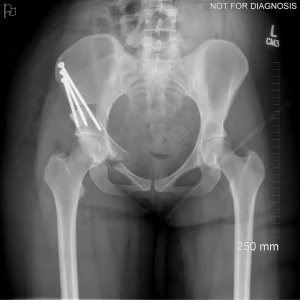

During a PAO, the surgeon carefully cuts the bone around the hip socket and repositions it to provide better coverage of the femoral head. The socket is then fixed in its new position using screws. The goal is to improve hip stability, reduce pain, and preserve the patient’s natural hip joint.

Diagram 3: Hip After Periacetabular Osteotomy (PAO)

• Acetabulum repositioned to improve femoral head coverage

• Load more evenly distributed across the joint

• Screws shown securing the acetabulum in its new position

Screw Removal

In most cases, the screws are left in place. However, if they cause irritation, removal can be considered after the bone has healed, which is typically 9-12 months after the initial PAO.